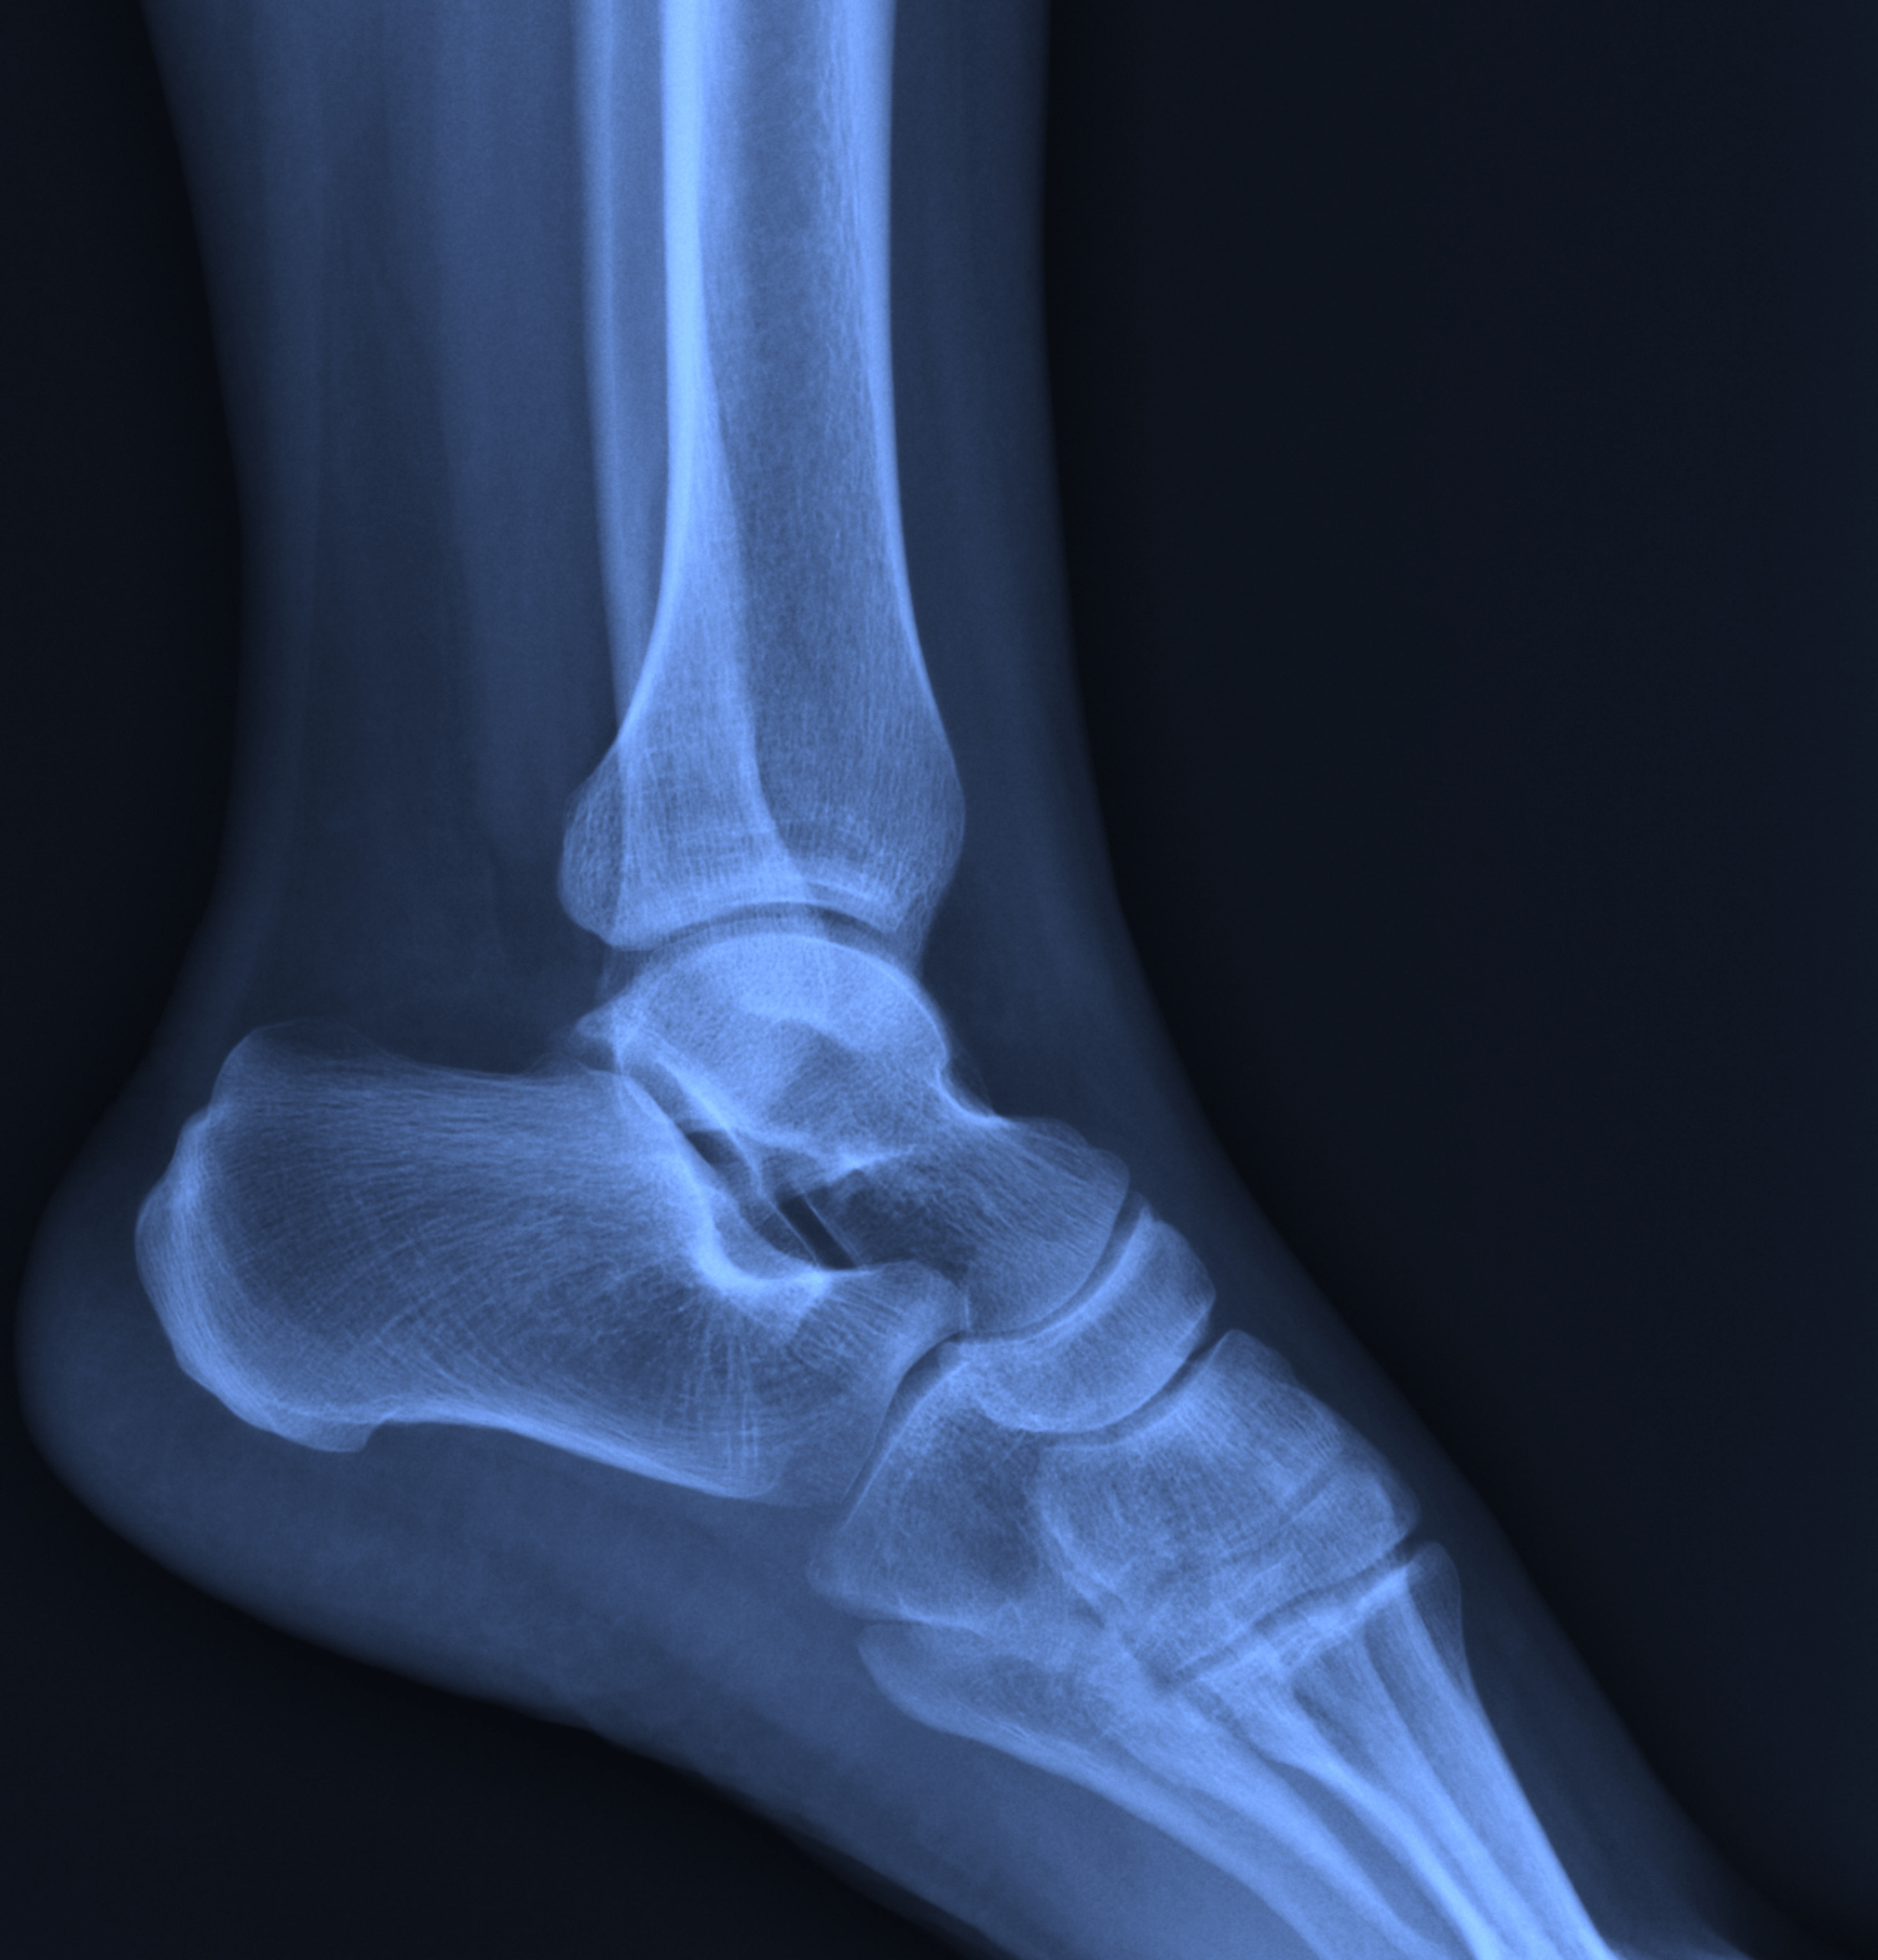

Radiografia della Caviglia a Domicilio

Radiografia caviglia

Che cos'è la radiografia alla caviglia ?

La radiografia della caviglia, o RX caviglia, è un esame diagnostico che utilizza i raggi X per creare immagini dettagliate delle strutture interne della caviglia.

Questo esame permette di visualizzare le ossa, che appaiono molto più chiare rispetto agli altri tessuti, e le articolazioni, che risultano più scure.

L'esame radiografico diretto della caviglia viene condotto utilizzando un fascio di raggi X che attraversa la caviglia e si imprime su una pellicola, creando un'immagine fotografica delle strutture interne.

La caviglia viene scansionata con un’apparecchiatura radiografica portatile, che può essere utilizzata sia in posizione distesa su un lettino che in piedi.

La radiografia della caviglia è utilizzata principalmente per individuare fratture ossee, lussazioni, artrite, e altre patologie che possono interessare le ossa e le articolazioni della caviglia.

È un esame di primo livello, spesso utilizzato come monitoraggio o preliminare ad altri esami più approfonditi, come la risonanza magnetica o la TAC.

La radiografia permette di vedere chiaramente le ossa, che appaiono bianche e compatte, mentre i tessuti molli risultano più scuri.

Questo contrasto aiuta a identificare anomalie come fratture, disallineamenti delle articolazioni, e segni di artrite.